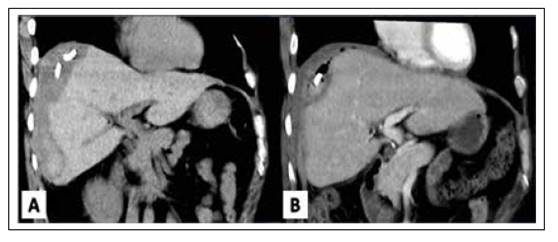

Se realizó un estudio de cultivo del contenido aspirado no evidenciándose gérmenes. Se realiza interdiariamente lavados de drenaje percutáneo con cloruro de sodio hasta el aclaramiento. En los días posteriores al procedimiento el paciente se mantuvo asintomático, apirético, hemodinámicamente estable y con buen estado general, sin evidencia de resangrado. Es dado de alta 2 semanas después de la colocación del catéter. Se realizaron ecografías abdominales posteriores y tomografía por vía ambulatoria para control evolutivo de la lesión (ver Figura 2) los cuales mostraron una disminución paulatina de la misma, siendo retirado el drenaje a las seis semanas sin evidenciarse complicaciones.